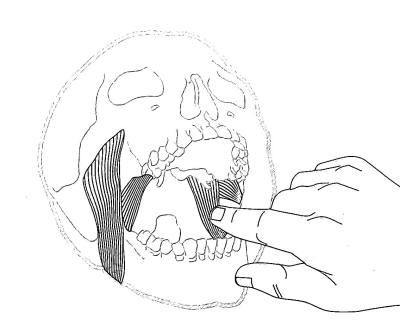

Palpación del músculo pterigoideo interno: |

Similar a la palpación del pterigoideo externo el dedo

índice ó meñique presiona sobre el pilar anterior en su zona

media y luego se desplaza hacia atrás. Para obtener

respuesta dolorosa solo hace falta una presión media |